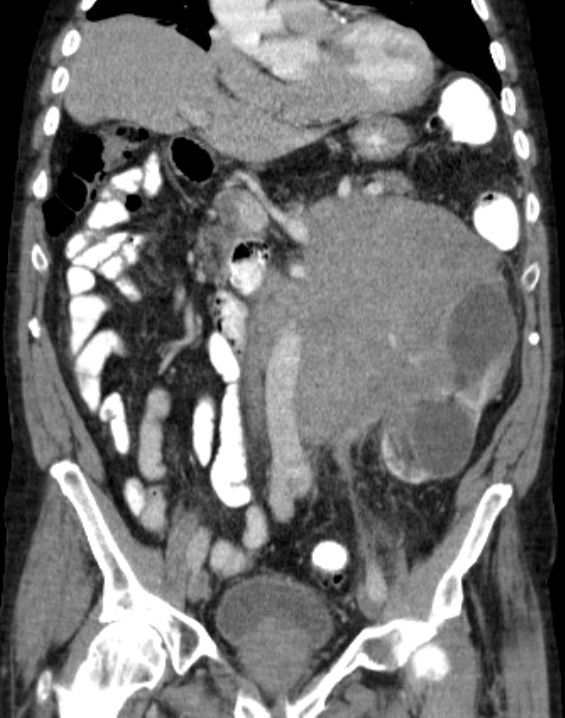

aortaler Bulk |

80-jähriger Mann mit einem retroperitonealen NHL.![]() |